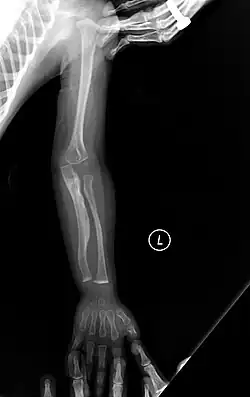

The main symptom of osteogenesis imperfecta is fragile, low mineral density bones; all types of OI have some bone involvement.[5] In moderate and especially severe OI, the long bones may be bowed, sometimes extremely so.[28] The weakness of the bones causes them to fracture easily—a study at the Endocrine Unit at the National Institute of Child Health in Karachi, Pakistan found an average of 5.8 fractures per year in untreated children.[29] Fractures typically occur much less after puberty, but begin to increase again in women after menopause and in men between the ages of 60 and 80.[1]: 486

Diagnosis

Diagnosis is typically based on medical imaging, including plain X-rays, and symptoms. In severe OI, signs on medical imaging include abnormalities in all extremities and the spine.[97] As X-rays are often insensitive to the comparatively smaller bone density loss associated with type I OI, DEXA scans may be needed.[5]: 1514

An OI diagnosis can be confirmed through DNA or collagen protein analysis, but in many cases, the occurrence of bone fractures with little trauma and the presence of other clinical features such as blue sclerae are sufficient for a diagnosis. A skin biopsy can be performed to determine the structure and quantity of type I collagen. While DNA testing can confirm the diagnosis, it cannot absolutely exclude it because not all mutations causing OI are yet known and/or tested for.[83]: 491–492 OI type II is often diagnosed by ultrasound during pregnancy, where already multiple fractures and other characteristic features may be visible. Relative to control, OI cortical bone shows increased porosity, canal diameter, and connectivity in micro-computed tomography.[98] OI can also be detected before birth by using an in vitro genetic testing technique such as amniocentresis.[99]